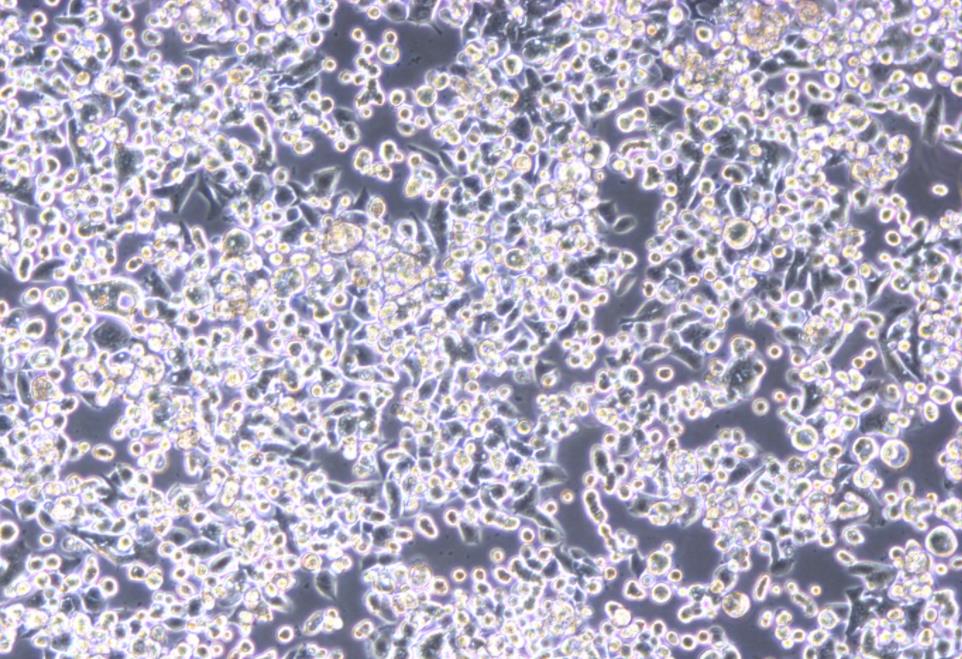

KATO III 细胞具有球形形态,是从一名 55 岁的亚洲男性胃癌患者的胸腔积液中体外建立的 |

形态 |

上皮细胞样 |

生长特征 |

贴壁,悬浮混合生长 |